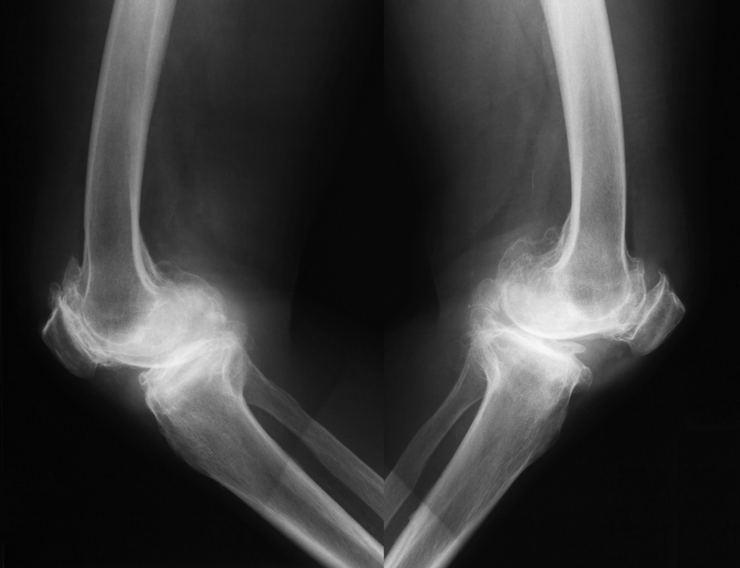

- Limon kabuğunu çöpe atıp limon suyunu ve meyvesini tüketirken aslında limon kabuğu ile birlikte sağlık için faydalı, hatta eklem ağrılarını ortadan kaldıracak bir çok besin maddesini de çöpe atmış oluyoruz.

- Limon kabuğunda bulunan esans yağları, k’an damarlarını rahatlatır ve eklemlerdeki ağrıları önemli ölçüde azaltır. Aynı zamanda iltihap sökücü etkisiyle de önemli bir besin kaynağıdır.

- Limonun kabuğu, k’an damarlarını yatıştıran ve anti-iltihap özelliklere sahip zengin özlü yağlarla doludur. Sinir ağrısını yok etmek için mükemmeldir.